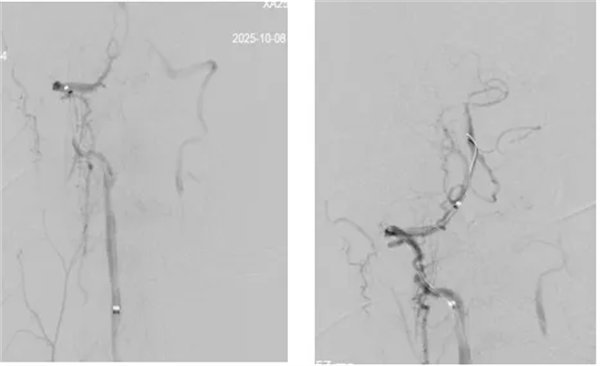

席聪准确锁定患者基底动脉处血栓,采用抽吸取栓技术快速开通血管,成功取出堵塞部位2cm的血栓。再次造影示:右侧大脑后及双侧小脑上动脉再通,右侧大脑后动脉P3段以远闭塞,考虑慢性闭塞,推注替罗非班,血流明显加快。随后采用支架植入术开通右侧椎动脉开口处,术中影像显示:支架贴壁良好,无明显残余狭窄,颅内血管显影良好。

术后,患者症状明显好转,神志清楚,右手无力、视物模糊症状明显改善,术后24 小时可下床活动,NIHSS评分1分,mRS评分2分。